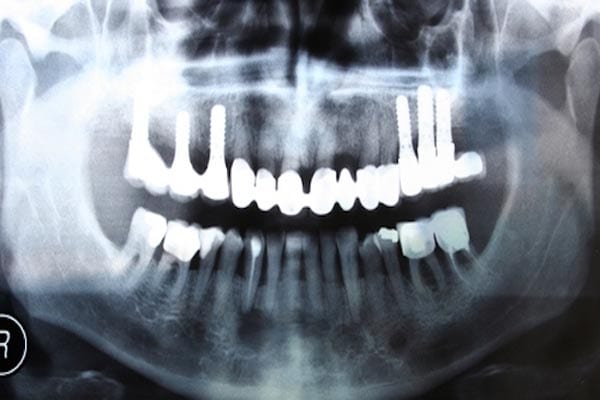

لا حاجة لزرع الأسنان بعد الآن. اجعلوا أسنانكم تنمو بنفسها في 9 أسابيع!!!

رئيس فريق جامعة كولومبيا الدكتور جيرمي ماو اكتشف طريقة واعدة لحل مشكلة الأسنان فهول يقول أن هناك طريقة مصنوعة من الخلايا الجذعية، هذه الطريقة ستسمح بان تنمو الأسنان من جديد، يقول ماو أن هذا الاكتشاف سينهي الحاجة إلى زراعة الأسنان .

ربما من الاسهل الذهاب إلى طبيب الأسنان وزرع واحد مكانه ولكن هذه الطريقة هل حل طبيعي لان السن سينمو من الخلايا الجذعية وهذه الطريقة مستعملة بكثرة في العظام المكسورة أو للاضطرابات الجينية.

تحتاج هذه الطريقة إلى 9 أسابيع حتى ينمو السن من جديد، وسيحتاج إلى سنة حتى يكتمل نموه، والرائع في هذه الطريقة أن الشخص لا يحتاج إلى زرع أو وضع أي مادة غريبة في السن.